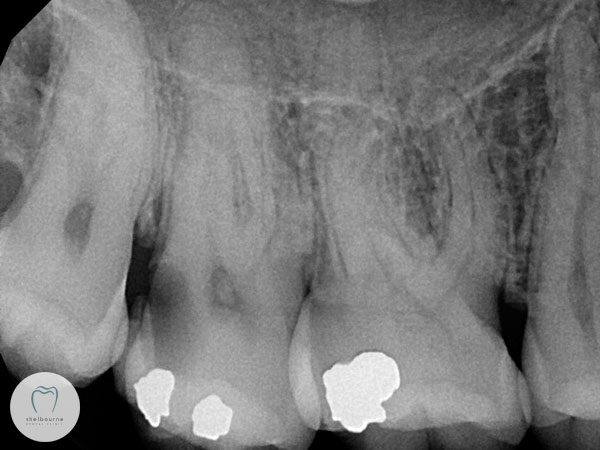

So having run out of other ideas and still unsure which tooth is the suspect, I took a digital x-ray. This lets me see what’s going on between teeth in particular, and under old fillings to some extent. And there we have it, a big dark decayed area on the back of the second molar.

I’ve highlighted the area on the image below as not everyone is used to reading x-rays! The red arrows show the decayed area. The blue arrow points to a separate dark area; that’s the nerve. This decay is way too close for comfort.

But go back and look at the first photograph again. There really was no sign of decay visible, and yet now we’re at the point of doing a complicated root canal treatment at a minimum, or quite possibly losing the tooth. Naturally I want to find something like this well before it gets to the point of no return. X-rays aren’t fool-proof either, but they’re another piece of the puzzle that lets us build up as comprehensive a picture as possible of your dental health, helping us make the treatment choices that most benefit you.